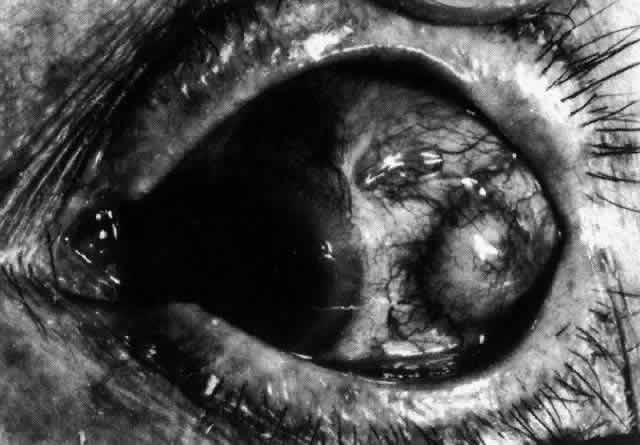

The angiogram is similar to that of diffuse anterior scleritis (i.e., there is a rapid filling pattern and deep scleral leakage of dye).26 Necrotizing Anterior Scleritis with Inflammation Patients with necrotizing anterior scleritis with inflammation not only suffer extremes of discomfort but are in serious danger of losing an eye. Therefore, it is of great importance that the condition be detected early and treated adequately. (It is of equal importance that those varieties of scleral inflammation that are not destructive to the eye should not be treated with drugs that are themselves dangerous.) Accurate diagnosis is the key. Necrotizing scleritis accompanied by inflammation is always painful, waking the patient at night, increasing in intensity day by day, and leading to severe distress. The sclera is swollen, and the overlying inflammation is localized to the center of a lesion or to either end of an extending lesion (Fig. 37; Color Plate 1D). After inflammation, the sclera becomes transparent so that the underlying choroidal pigment becomes visible when viewed in daylight (Fig. 38). These areas may be invisible with the slit lamp. The area of inflammation extends outward around the globe from the original site of inflammation, often joining with other areas of scleritis that have subsequently appeared. If the inflammation is not suppressed, the process will progress around the globe until the whole anterior segment is involved (Fig. 39).

The characteristic features of necrotizing scleritis on fluorescein angiography are hypoperfusion and, eventually, nonperfusion of the vascular networks (Figs. 40 through 43).26 The initial changes are on the venous side of the capillary network; the transit time of the dye increases even if the eye is red and congested. If the disease process persists or has been present for a long time, thrombosis and permanent vaso-occlusive changes occur. These vessels (or the occluded capillary network) are bypassed by the opening of anastomotic channels. New vessels in a granuloma give rise to deep intrascleral leakage of dye (see Fig. 43). Conjunctival and episcleral involvement by the destructive change is late but is always preceded by vaso-occlusive changes that can sometimes be detected with use of the red-free light on the slit lamp (Figs. 44 and 45).